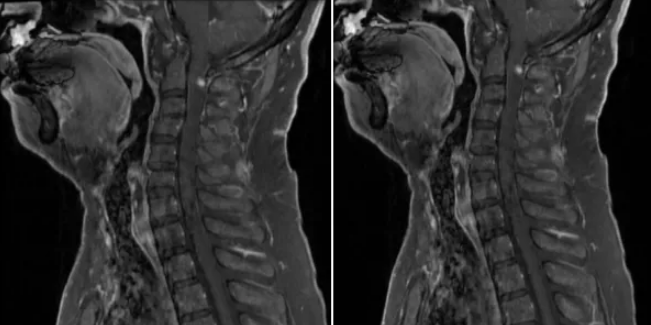

颈髓平扫示:C2-4水平颈髓内见片状稍长T1、T2、高STIR信号,长约3cm。

颈髓增强扫描示:C2-4颈髓病变增强扫描病变上缘见斑片状明显强化,边界欠清。